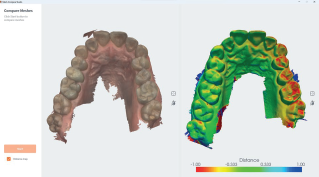

Buccal Monitoring

This type of monitoring guides the dentist in observing changes over time in the patient’s mouth.

Quality Map

An exclusive tool allowing instantaneous scan quality check and live rescan if necessary to complete impression.

Occlusal Clearance

This tool helps you check the clearance before exporting the case in order to help you treat your crown and bridge patients in an effective and predictable manner.